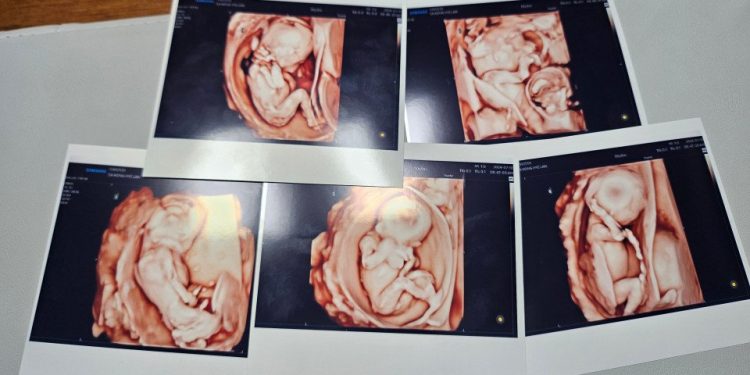

기쁨도 잠시 부부는 ‘팡팡이’가 둘이나 셋도 아닌 다섯 쌍둥이라는 사실을 알게 됐다. 하지만 다섯 아이를 모두 지켜야겠다는 결심을 했고, 태명도 다섯으로 구성된 파워레인저에 빗대어 ‘팡팡레인저’로 지었다.

‘팡팡레인저’의 출산 예정일은 12월이었지만 체구가 작은 산모의 배는 이미 만삭처럼 불러왔고 임신 합병증으로 고혈압성 질환인 전자간증이 진단돼 출산을 더 미룰 수 없게 돼 27주에 제왕절개 수술을 해야 했다.

이렇게 이날 오전 11시37분 첫째(969g)가 세상 밖으로 나왔고, 둘째(888g), 셋째(953g), 넷째(736g), 다섯째(781g)까지 수술실 내 처치를 마치자마자 안전하게 집중치료실로 이동을 마쳤다. 3남 2녀였다.